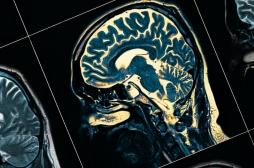

LES MALADIES

SYMPTÔMES